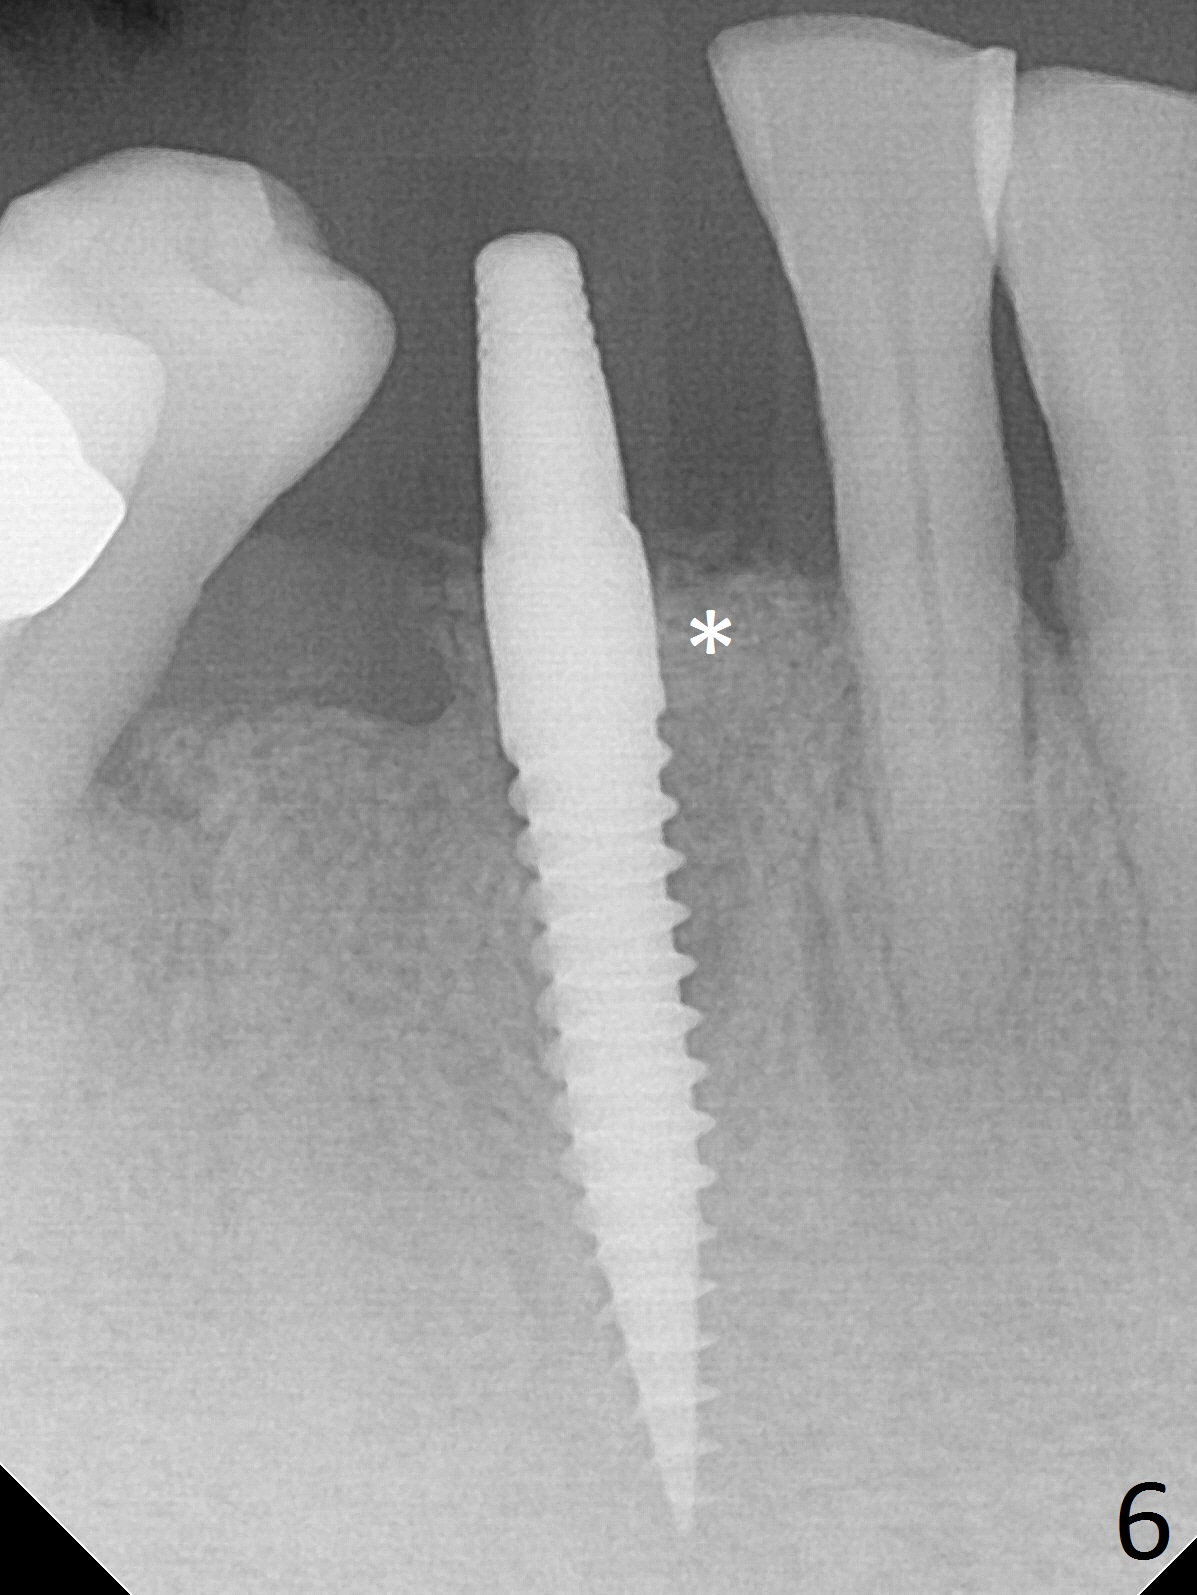

The lower dentition is special, consisting of a residual root (Fig.1 ^), 2 incisor (I), 1 canine (C), 1 premolar (P) and 1 molar (M). The residual root looks like an incisor with rotation of 90º (Fig.2,3). Osteotomy is initiated (Fig.4) for a 3x16(2) mm 1-piece implant (Fig.5 with 45 Ncm). The implant is being placed as distal as possible (Fig.4 arrow) so that a large canine-like provisional is to be fabricated in the large edentulous space (Fig.8,9) after bone graft (Fig.6,7 *). The gingiva around the provisional (Fig.10 P) remains healthy 11 days postop with occlusal clearance against the opposing dentition (Fig.11). The implant threads are not exposed with the help of bone graft 3 months 1 week postop (Fig.12). The gingiva around the implant is healthy (Fig.13). Soft tissue socket is formed by the provisional (Fig.14 *).